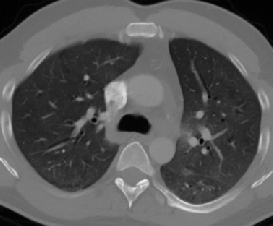

Figure 1 shows four CT scan slices, two from a non-COVID-19 CT scan, on the left and two from a COVID-19 scan, on the right. Bilateral ground glass regions are seen especially in lower lung lobes in the COVID-19 slices.